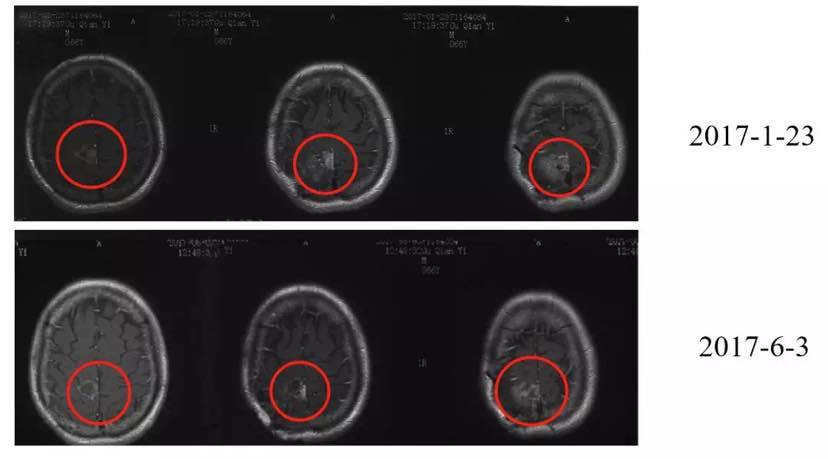

三次手术、靶向治疗并没有驱赶走病魔,患者病情逐渐恶化。2017年1月23日,其脑内右侧顶叶检测出一个大小为3.2×2.8cm的肿块,同时脑膜多发转移。

颅内多发病灶,2017年2月15日,在医生的权衡之下,患者开始尝试头部放疗联合靶向药安维汀治疗。2月15日至3月13日,共进行17次放疗。